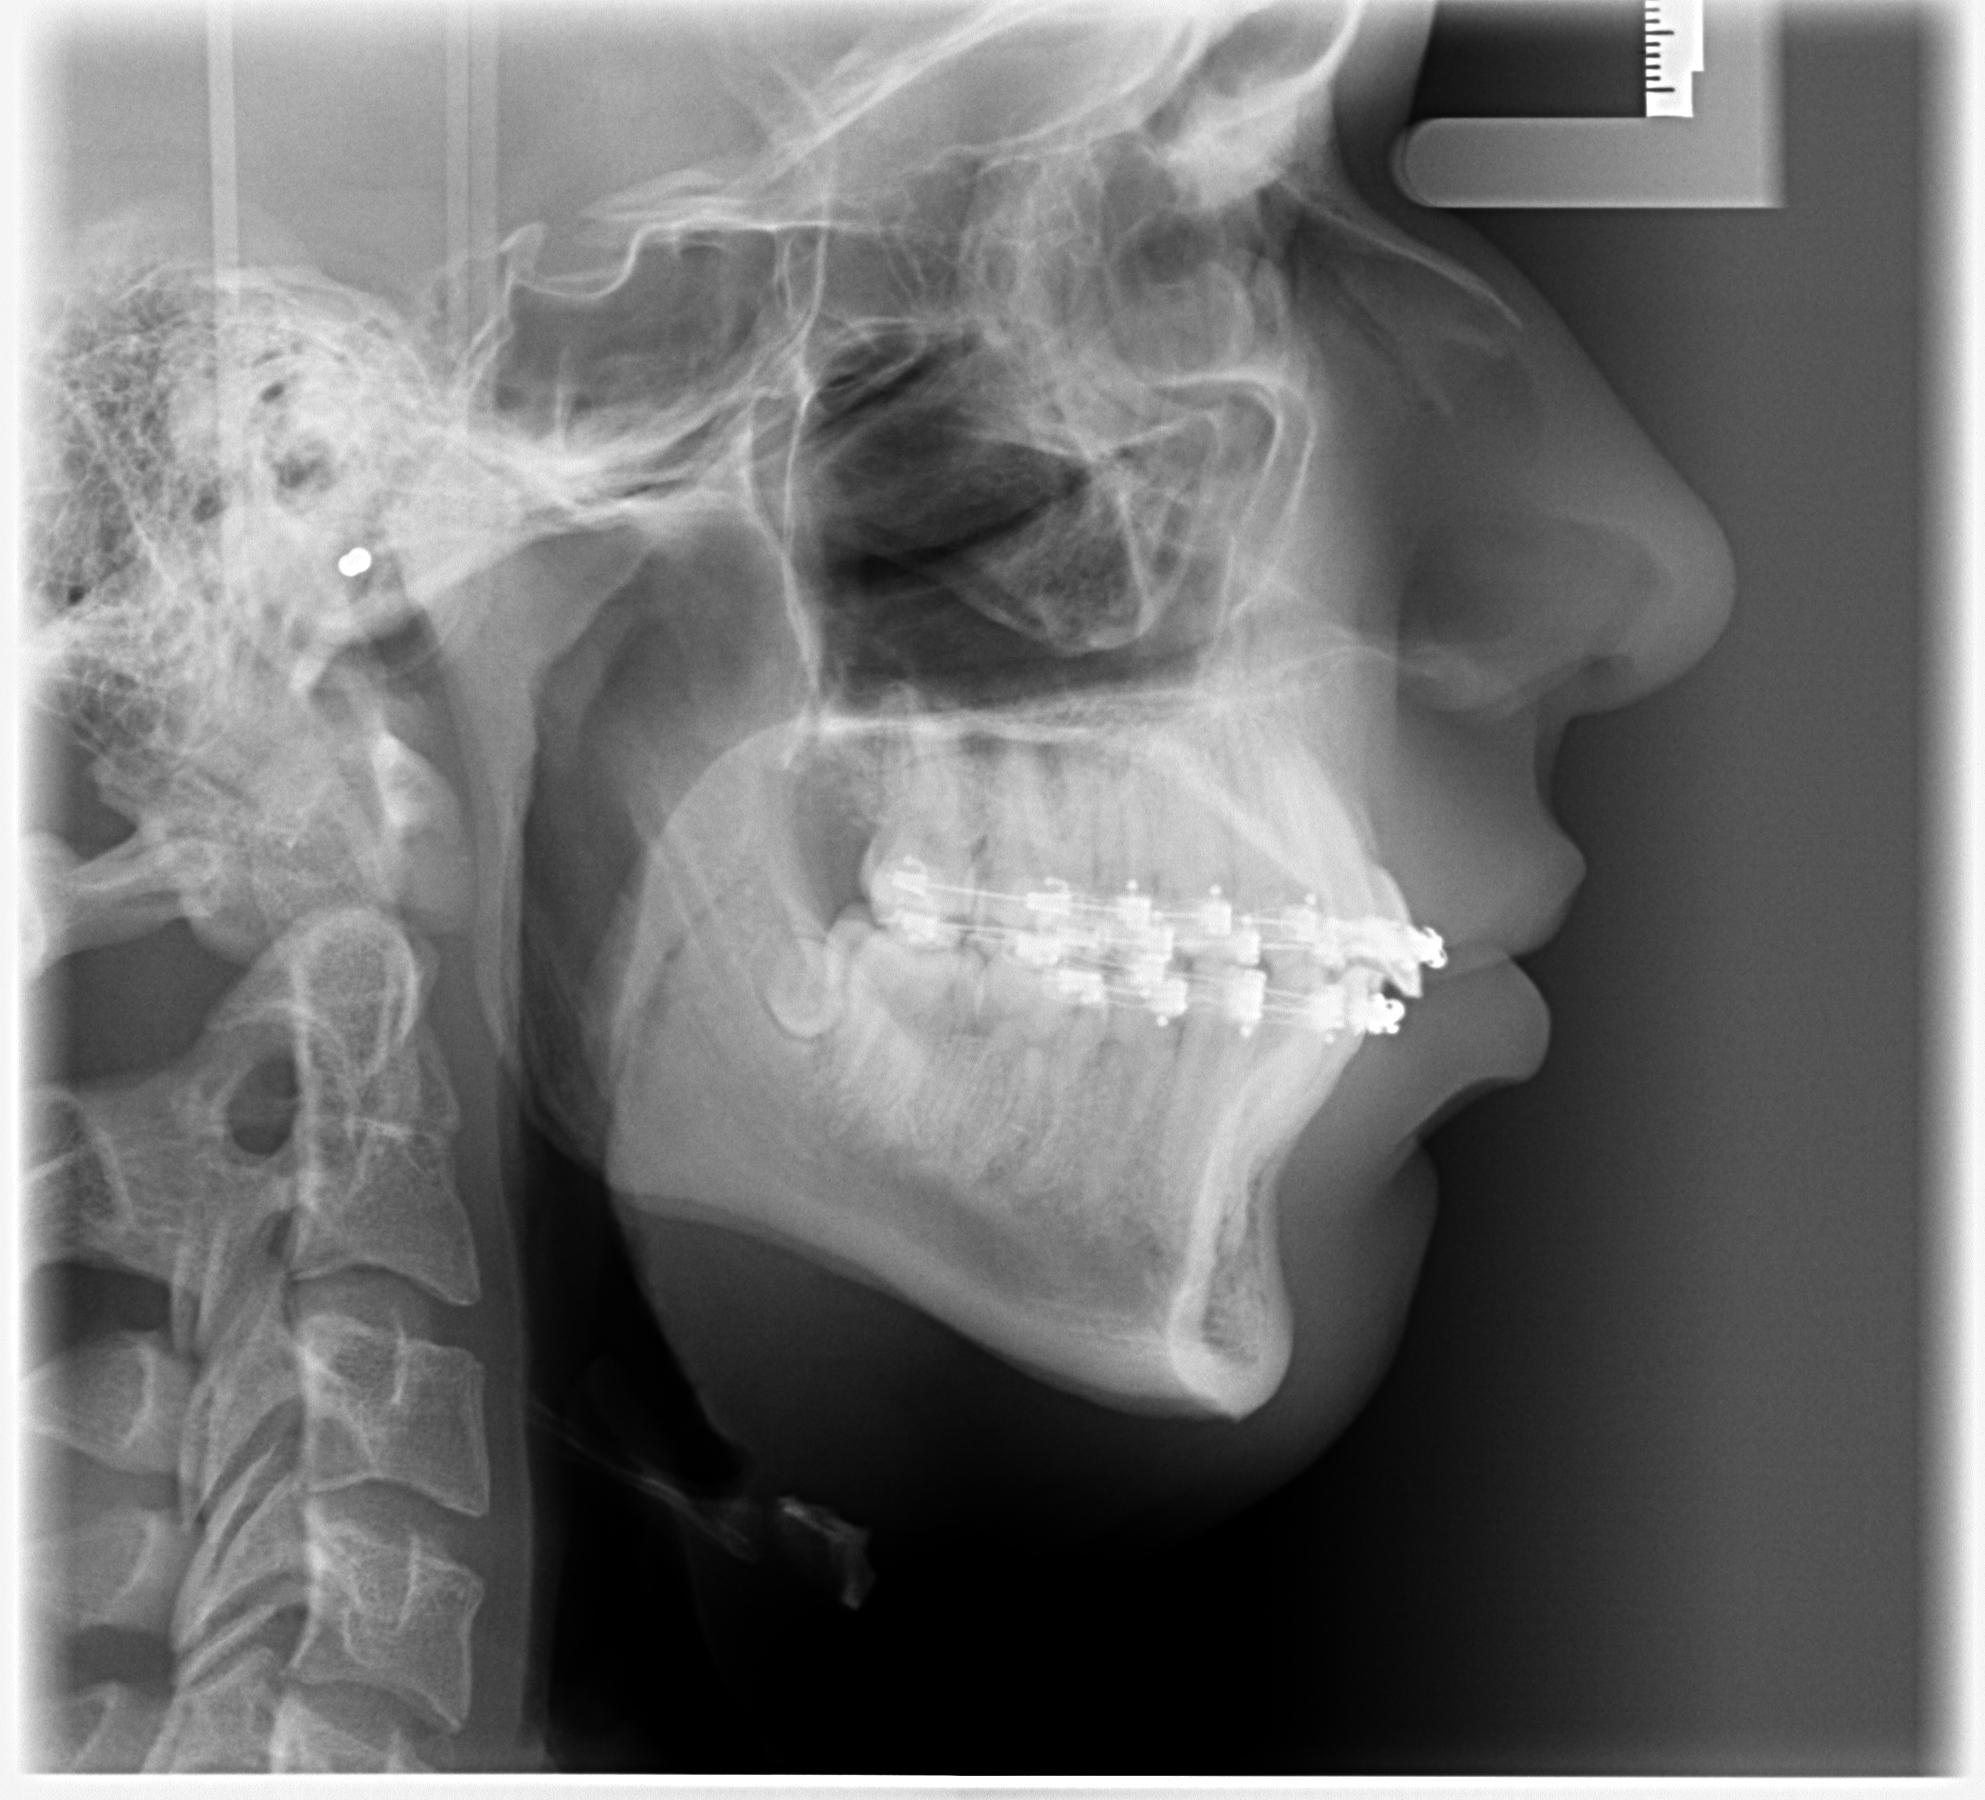

I got bimax surgery + genioplasty 3 days ago at age 17.

Before pictures:

Before pictures: